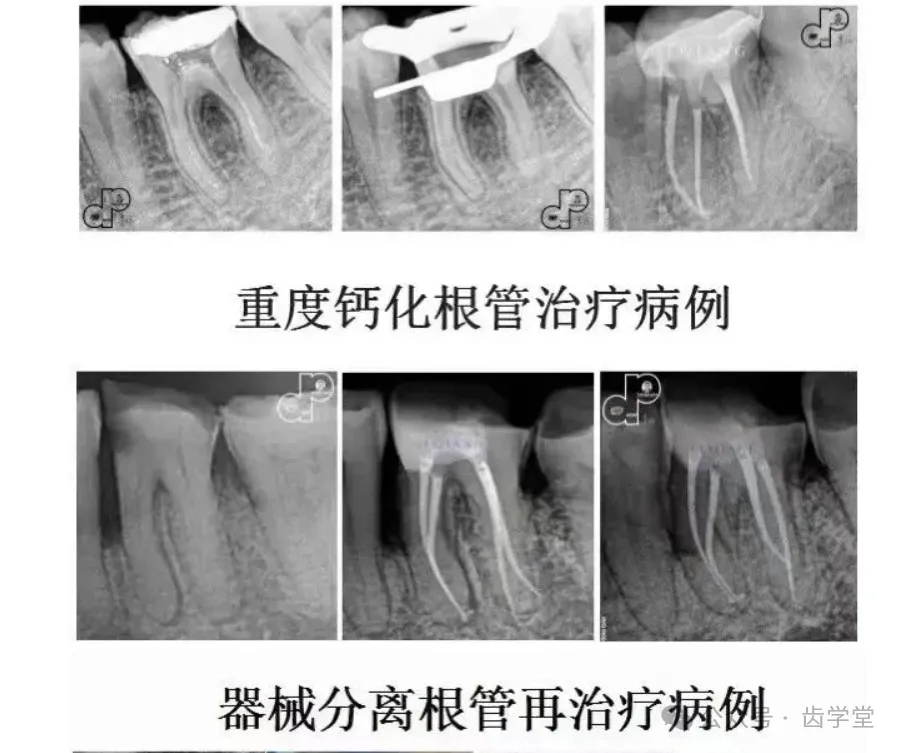

3. 变异根管口的精准定位与微创暴露技术:针对钙化、偏移或隐匿性根管口,解析显微镜下的定位逻辑与微创暴露技巧,降低医源性损伤风险。

6. 弯曲根管的阶梯疏通与安全预备技术:从预弯器械选择到逐步深入的操作流程,规范弯曲根管的疏通要点,降低台阶、侧穿等并发症风险。